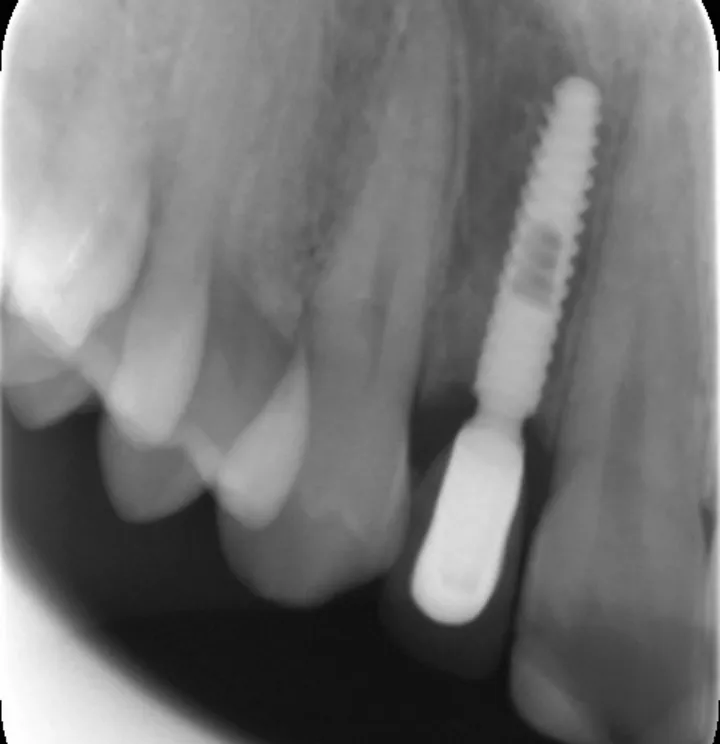

图 26 :术后 X 线检查。